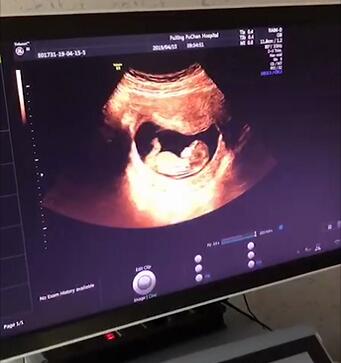

NT检查是什么?

NT检查,是实现优生优育必要的检查。NT,即胎儿颈部透明层,是指在孕11~13W+6天利用超声观察并测量胎儿颈背侧软组织与皮肤之间的厚度,评估胎儿染色体异常发生的风险率。

nt.jpg